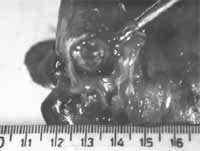

Figura 1. Tumor carcinoide endobronquial de localización central.

Los carcinoides pueden ser centrales o periféricos (2), y su localización no se relaciona con el tipo histológico del tumor. Entre un 16 – 40% de los tumores carcinoides son periféricos (8), y se localizan a nivel subpleural sin relación anatómica con el bronquio (8). De igual forma pueden aparecer asociados a la fibrosis pulmonar idiopática, así como a los adenocarcinomas (2).

Cortesia del Dr. Carlos Garavito, Cirujano de Tórax, Hospital Santa Clare E.S.E.